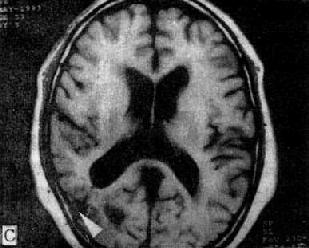

MRI 适宜于观察CT扫描为等密度的亚急性脑内血肿,已如前述。脑梗塞的发现MRI比CT扫描要早,一般起病后6小时MRI即可出现异常。脑干和小脑腔隙性梗塞灶的探测,MRI明显优于CT。脑梗塞灶在T1WI上呈低信号,在T2WI上呈高信号(图5-1-6C、D)。

MRI不需注射造影剂便能直接观察动脉瘤的瘤壁和瘤内血栓(图5-1-6E、F)、血管畸形的供血和引流血管、畸形血管团以及继发性改变,例如脑出血、缺血和软化等情况。但动脉瘤和血管畸形在手术前一般还需作脑血管造影或DSA,以便详细了解脑的供血和脑循环情况。

图5-1-6 MRI扫描SE序列图像

在矢状面(A)和冠状面(B)T1WI可见垂体肿块向鞍上延伸,呈等信号区(→);在横断面T1WI(C)和T2WI(D)上分别可见左枕和右基底节区脑梗塞灶呈低和高信号区(→);在矢状面T1WI(E)和横断面T2WI(F)上,可见基底动脉瘤环形影,其内为低信号和高信号区,高信号区为瘤内血栓形成(→)